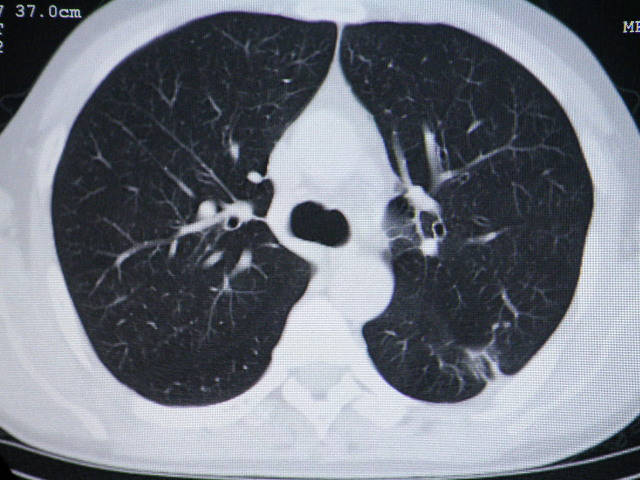

肺内结节在纵隔窗内测ct值为43hu

来源于肝脏mt伴淋巴结肿大,肺内病灶无纵隔窗,mt首先考虑.

左肺下叶背段软组织结节,偏心空洞,周围见长纤维所条及卫星灶,首先考虑结核球,周围型肺癌待排。

左肺下叶偏心软组织肿块,边缘毛刺征,胸膜凹陷征

手术效果不会太好,腹腔病变考虑恶性间质瘤,肺内结节肺癌可能性大,(楼主未提供纵隔窗,结核不能除外)最好术前明确诊断.

有肝硬化背景,肝胃间隙见不规则形,且密度不均匀的占位性病变,与肝左叶分界不清,首先考虑外生性肝癌可能性大,不排外肝胃间隙恶性占位肝脏受侵可能性。左肺下叶结节影,其内见空泡征,边缘见毛刺,从一元化的角度首先考虑转移。

1 肝脏各叶比例失调,形态失常,外缘呈波浪状。右叶萎缩,左叶 尾叶增大。2 腹腔内软组织密度肿块,低于肝实质密度,内见低密度区,并与肝脏界限欠清。腹膜后见肿大淋巴结,并与腹腔肿块关系密切。3 左肺下叶肿块,见边缘毛刺征及胸膜凹陷征,并与近肺门侧见异常血管相连。

综合考虑:左下肺周围性肺癌伴腹腔 腹膜后淋巴结转移!另:肝硬化!

左肺下叶偏心软组织肿块,边缘毛刺征,胸膜凹陷征,血管集束症

1肝胃韧带区域一肿块,肿块上缘与肝左叶相连。肝硬化。考虑肝外生型肝癌可能性大,不除外间质瘤。2左肺下叶背段一结节,有偏心性空洞,长毛刺,其周有多发小结节。考虑结核可能性大。

,腹腔病变考虑恶性间质瘤,肺内结节肺癌可能性大,(楼主未提供纵隔窗,结核不能除外)最好术前明确诊断.

那肺内病灶如何处理?

肝脏考虑外生型肝癌、肺内考虑结核,应该增强扫描